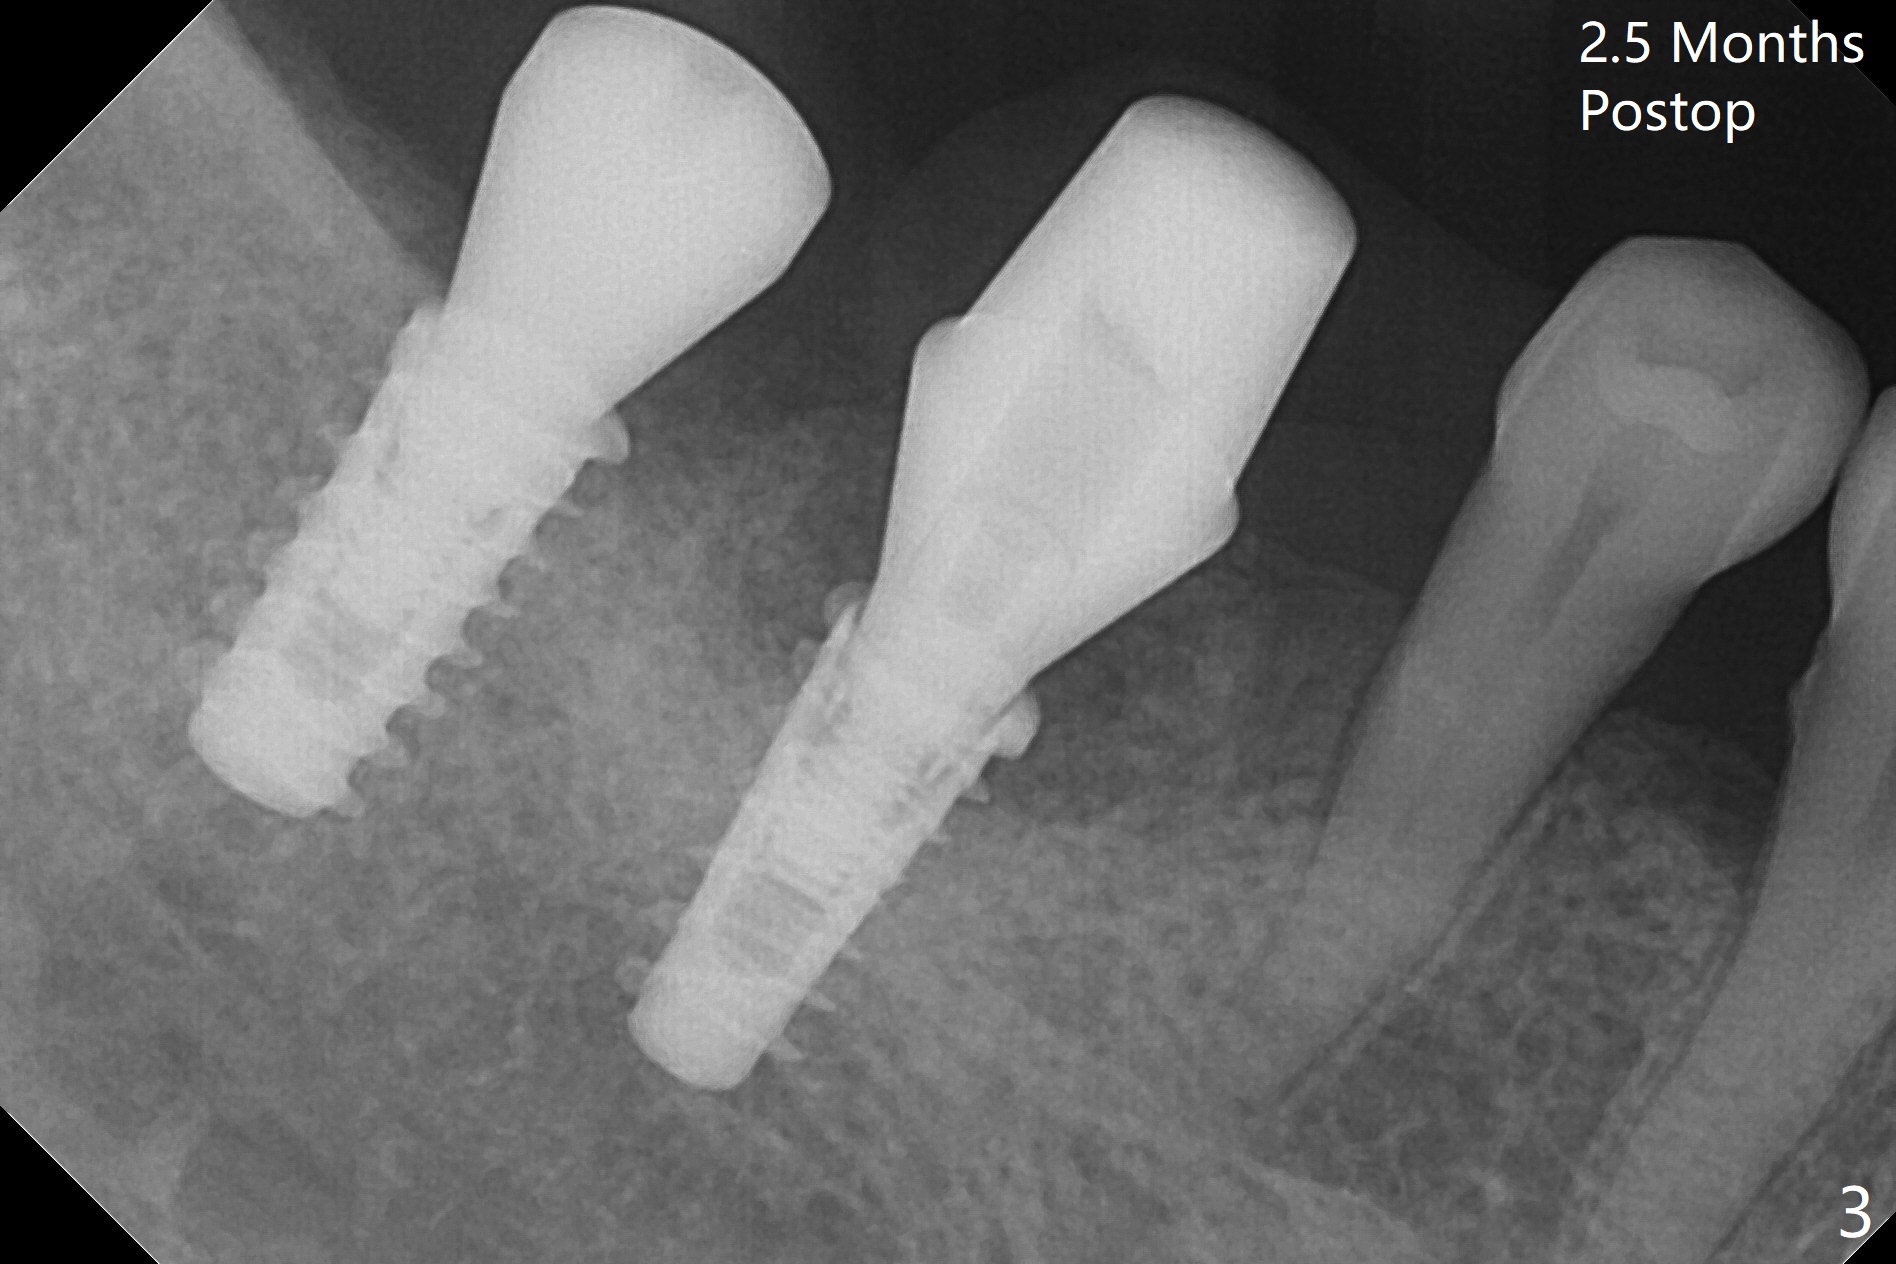

Following osteotomy, 4.5x11 and 5x9 mm dummy implants are placed at the sites of #30 and 31, respectively (Fig.1). Due to limited inventory of Magicore and patient's in-cooperation, FC implants (4.5x9 and 5x9 mm) are placed (Fig.2). A healing abutment (6x4 mm) is placed at #31 because of low torque (overprep), while a pair abutment (6.5x5.7(4) mm) is placed at #30. Vera Graft is placed with autogenous bone (*). The implant/abutment ratio at #30 is unfavorable. If the implant turns out to be loose, immediate implant should be larger in the future. Note bone growth, especially at #30, 2.5 and 4 months postop (Fig.3,4). In fact the abutments are incompletely seated. The crown of #30 is loose 2 years 8 months post cementation, while the abutment at #31 remains incompletely seated (Fig.5). The latter is completely reseated after separating the crown, while a smaller one is seated at #30 (Fig.6) due to use of a small healing abutment earlier (Fig.5). A good piece of news is the presence of the bone between the implants (Fig.5,6 *), which contributes to interimplant papilla. Return to Lower Molar Immediate Implant, Prevent Molar Periimplantitis (Protocols, Table), IBS77, 2-5 Xin Wei, DDS, PhD, MS 1st edition 09/22/2017, last revision 12/01/2020